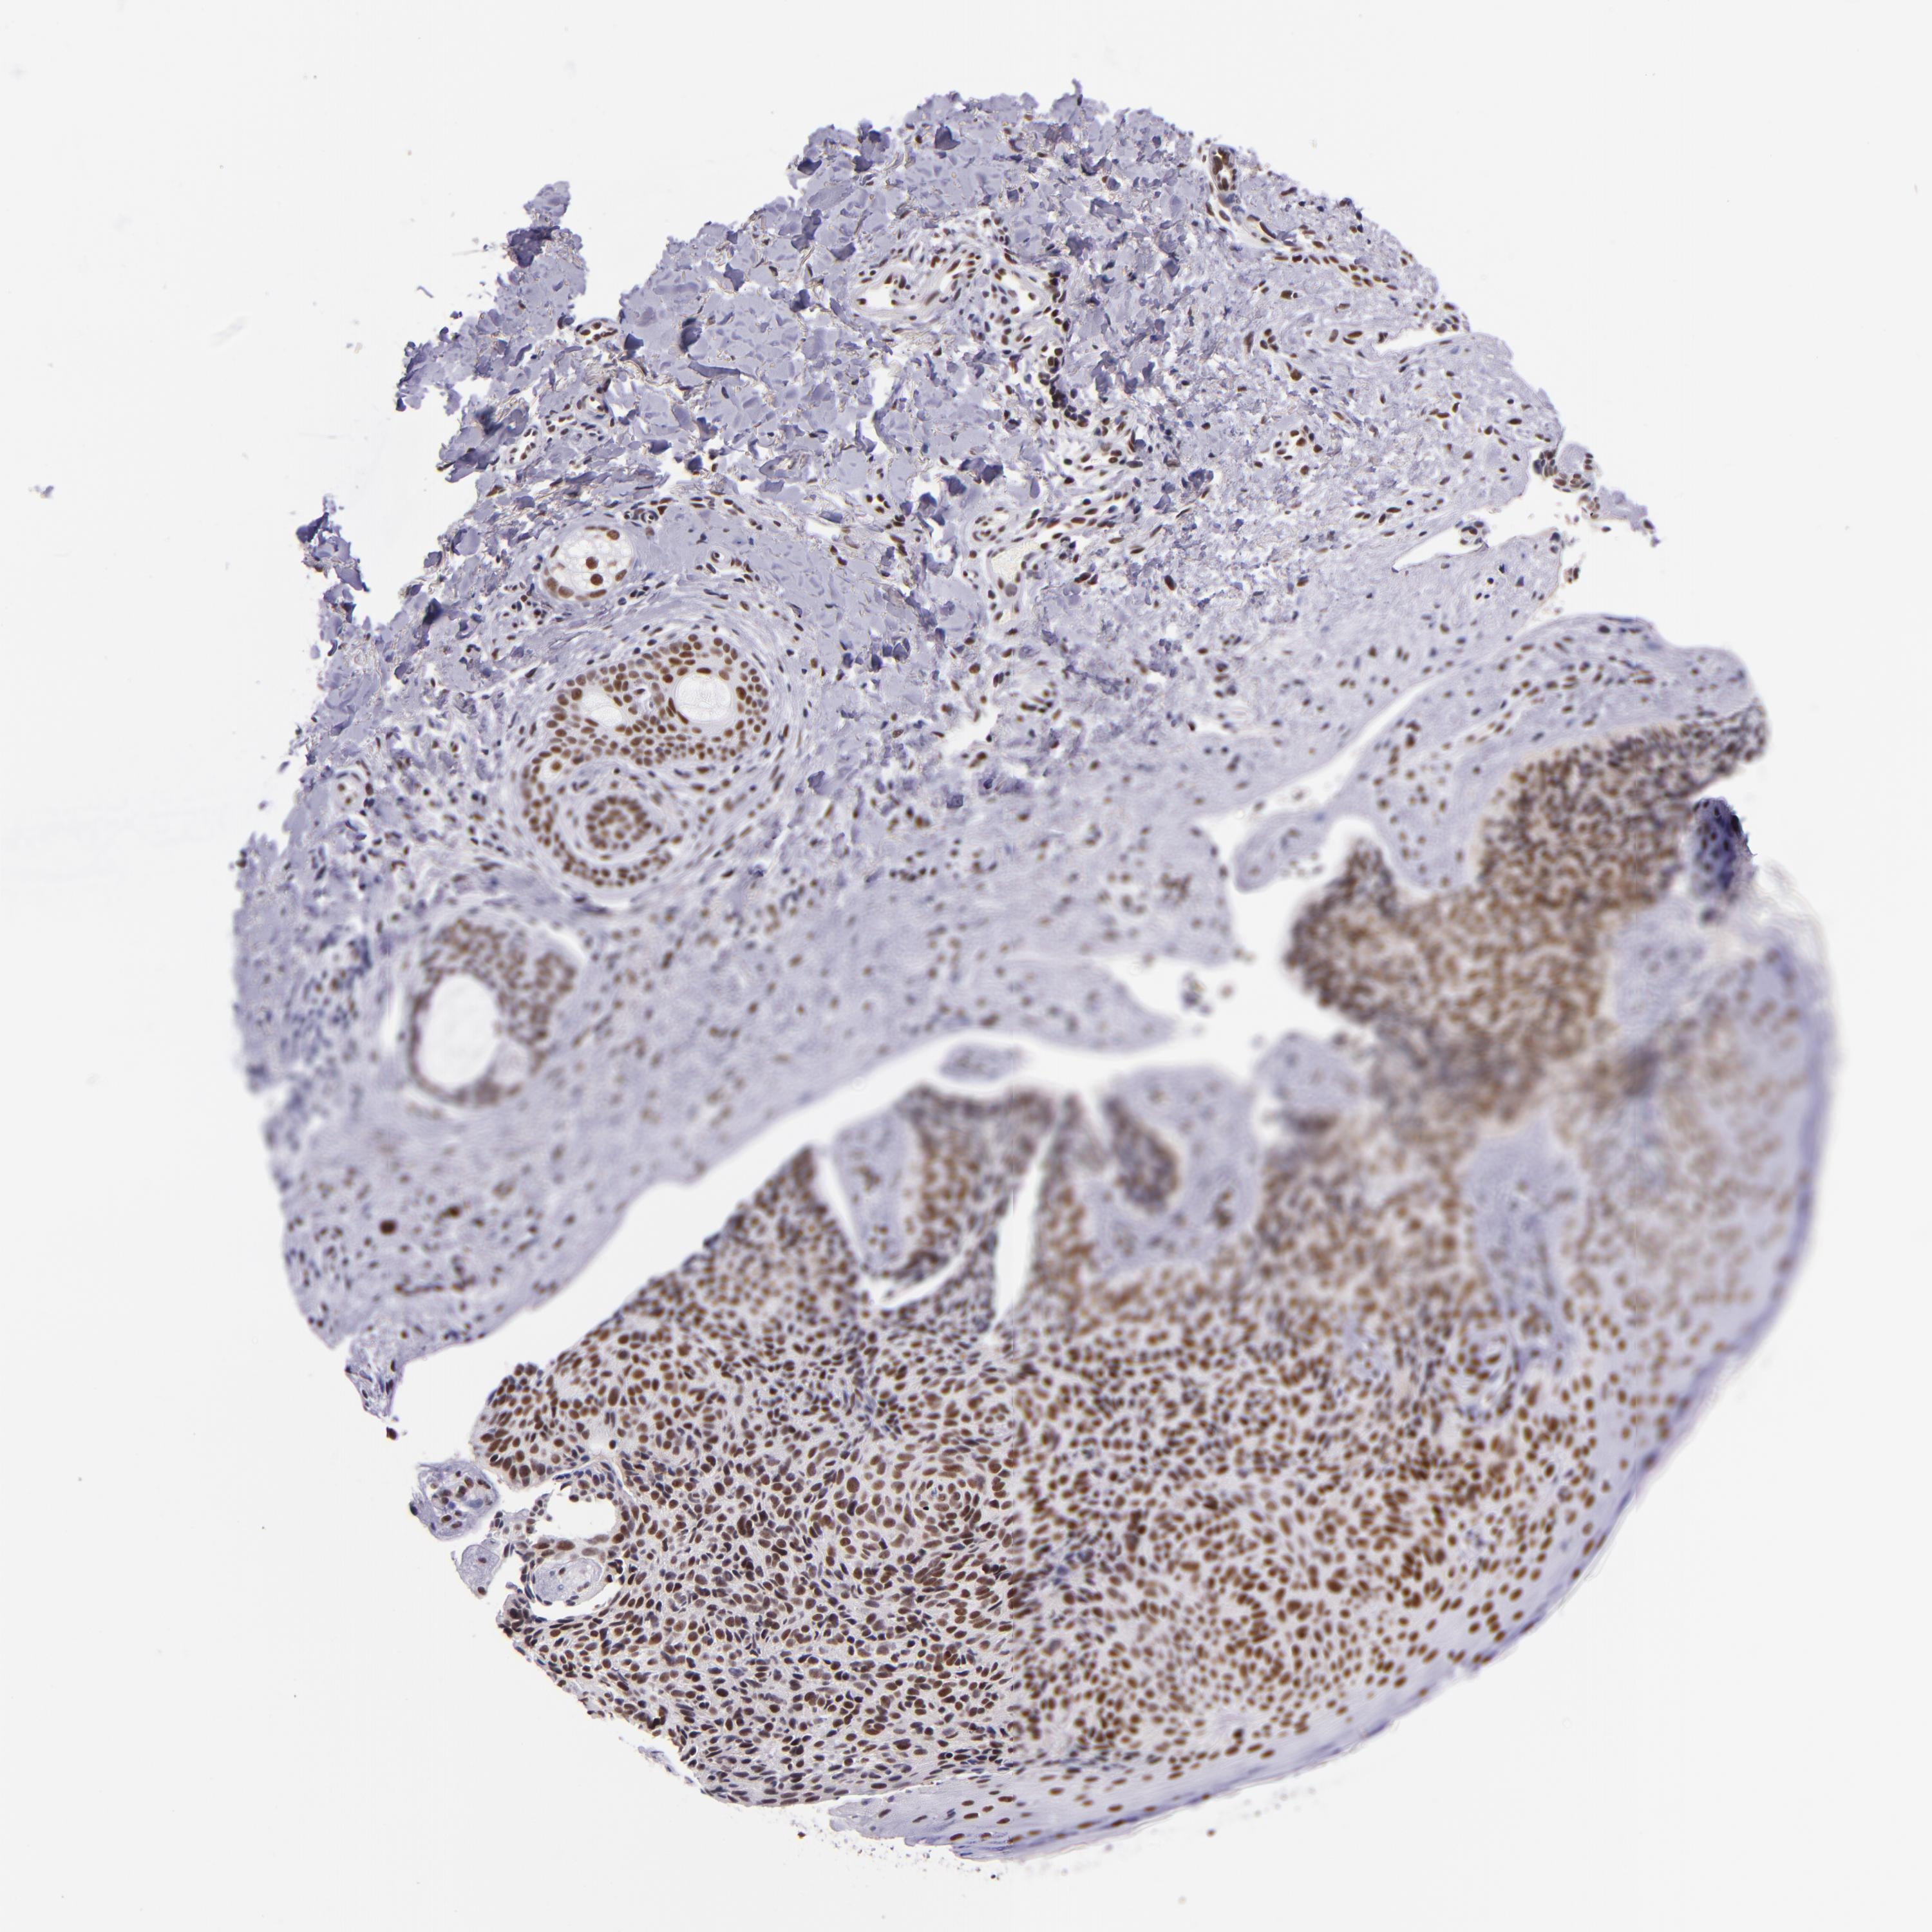

SKIN CANCER - Protein expressioni

A mouse-over function shows sample information and annotation data. Click on an image to view it in a full screen mode. Samples can be filtered based on level of antibody staining by selecting one or several of the following categories: high, medium, low and not detected. The assay and annotation is described here.

Each image is clickable and will lead to virtual microscopy that enables deeper exploration of all samples and also displays staining intensity scores, fraction scores and subcellular localization as well as patient and tissue information for each sample.

Antibody HPA000287

Antibody HPA001894

Staining

High

Medium

Low

Not detected

Intensity

Strong

Moderate

Weak

Negative

Quantity

>75%

75%-25%

<25%

None

Location

Nuclear

Cytoplasmic/membranous

Cytoplasmic/membranous,nuclear

Squamous cell carcinoma, NOS

Basal cell carcinoma